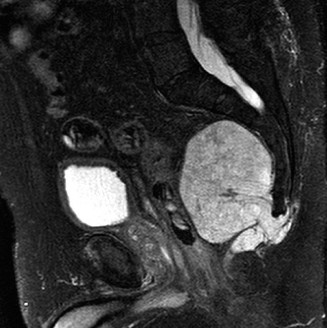

Diagnostic workup primarily relies on plain radiographs, which typically reveal a well-defined, lucent intramedullary lesion with punctate or ring-and-arc calcifications, endosteal scalloping, and cortical thinning. Periosteal reaction is usually absent unless a pathologic fracture has occurred. Magnetic Resonance Imaging (MRI) can provide further characterization, demonstrating the cartilaginous matrix with high T2 signal intensity and characteristic lobular morphology, aiding in differentiation from other lesions and assessing the extent of cortical involvement. Computed Tomography (CT) may be useful for intricate surgical planning or when assessing complex cortical defects or subtle matrix calcifications. Biopsy (incisional or excisional) is reserved for cases where the diagnosis remains uncertain, or there is clinical and radiological suspicion of malignant transformation (e.g., rapidly enlarging lesion, significant pain, cortical destruction, aggressive periosteal reaction).